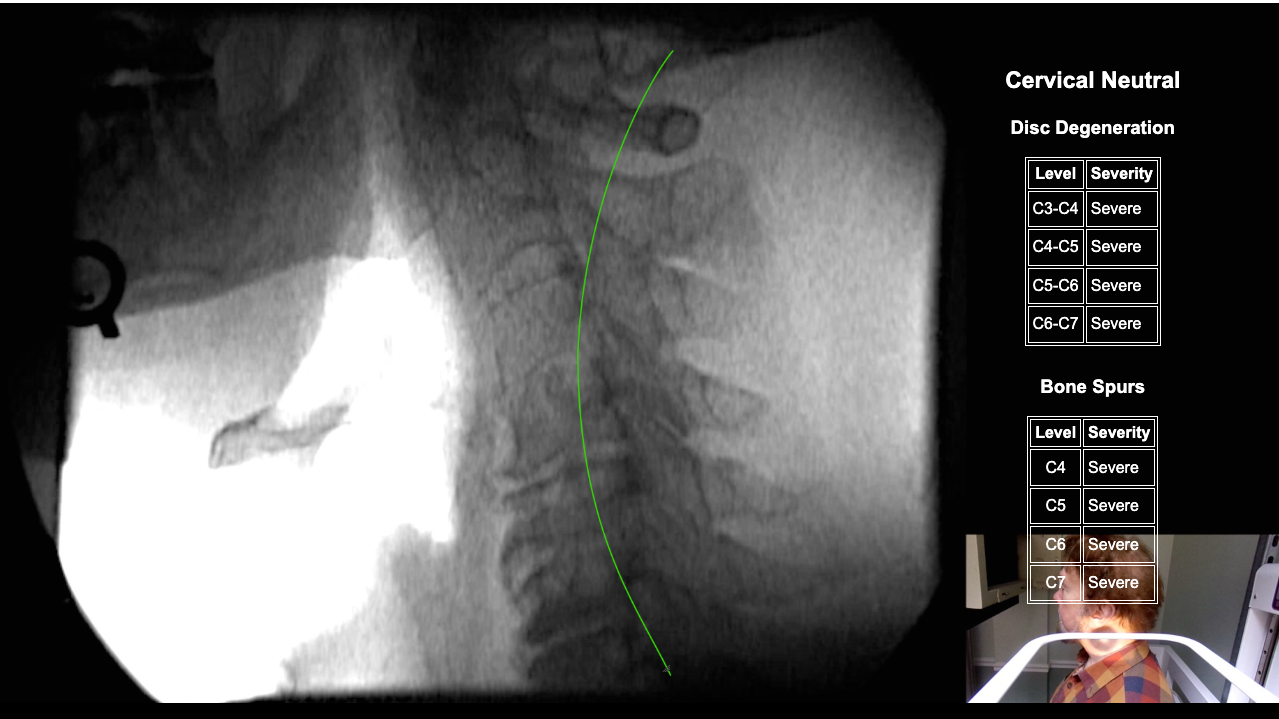

Home > Edward Hanlon DMX 2-12-26